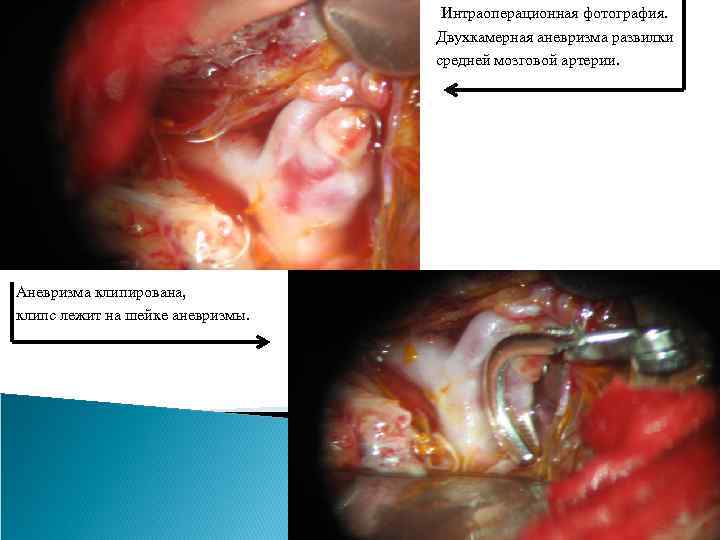

Методы лечения аневризм сосудов головного мозга. Определение аневризмы сосудов мозга является прямым показанием к проведению лечения, которое является исключительно хирургическим: - клипирование аневризмы (открытые вмешательства), - эндоваскулярное вмешательство Клипирование аневризмы. Целью внутричерепного (открытого) вмешательства на аневризме является выключение ее из кровотока при сохранении проходимости несущего и окружающих сосудов, удаление крови из субарахноидального пространства. Эти операции относятся к ряду наиболее сложных операций в нейрохирургии. Операция должна быть минимально травматична, что обеспечивается выполнением оптимальных хирургических доступов, микрохирургической техники и одномоментным клипированием шейки аневризмы. Для выполнения операции используется операционный микроскоп, специальный микрохирургический инструмент. При открытом вмешательстве, проведенных в условиях специализированных отделений крупных центров, летальность после операции в остром периоде кровоизлияния составляет 8 -16%, а в хроническом периоде кровоизлияния (через 1 месяц после него) – не более 2 -3%.